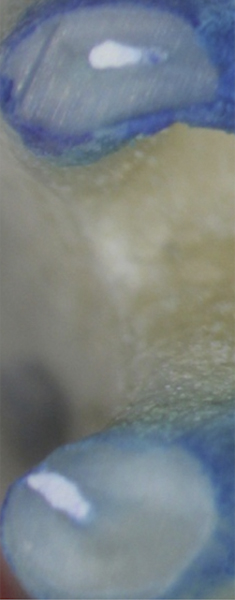

Figure 1. THROUGH Figure 3. Root filled with bioceramic sealer cut at different distances from the apex (left to right: 0.5, 1.5, and 3.0 mm). One gutta-percha point is used as a plugger to move the sealer using hydraulic pressure. Note the irregularities are very well filled.

Figure 1

Figure 2

Pre-mixed BC Sealer is the only pure medical-grade bioceramic product available as a sealer for endodontic obturation. It has the same basic chemical composition as the other pre-mixed bioceramic products, but it is less viscous, which makes its consistency ideal for sealing root canals. It is used with a gutta-percha point, which is impregnated on the surface with a nano particle layer of bioceramic. The gutta-percha is used primarily as the delivery device (plugger) (Figure 1 through Figure 3) to allow hydraulic movement of the sealer into the irregularities of the root canal and accessory canals (Figure 4 and Figure 5).